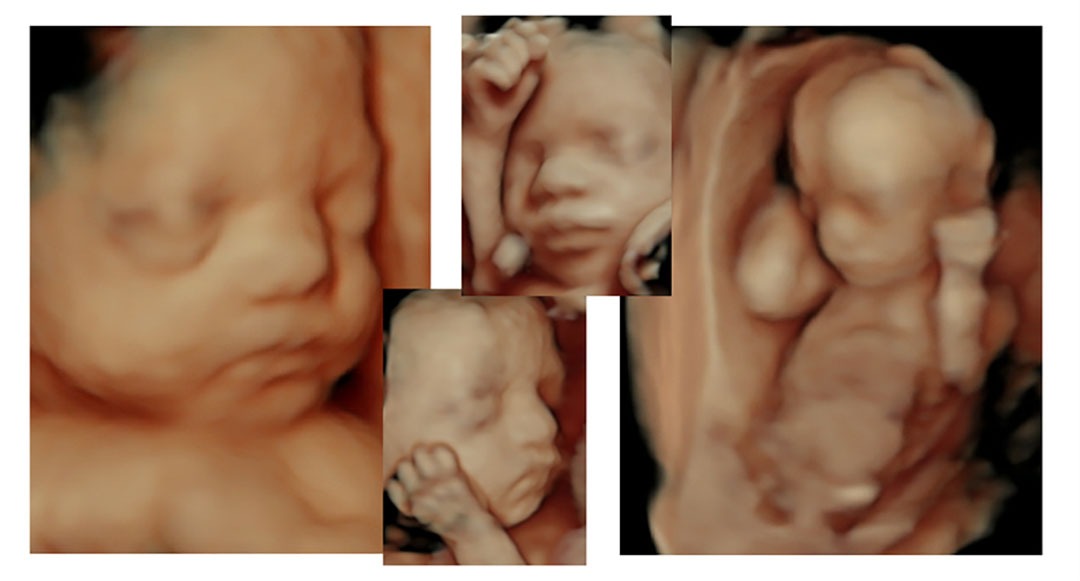

Ultrasound has been around for over 50 years. Unlike x-ray, ionizing irradiation is not present in ultrasounds which makes it a favorable and popularly modality. Ultrasound is sound waves. 2D ultrasound remains the standard in most diagnostic environments, but 3D ultrasound and 4D ultrasound is now being used for advanced diagnostic purposes and perinatologists, OB/GYN, and elective ultrasound facilities are using it for non-diagnostic purposes as well for its amazing bonding and psychological benefits. According to a publication on the Effect on Maternal Fetal Bonding, 3D ultrasound pictures appear to have a more positive influence on mothers towards their babies and more specifically, mothers who had a 3D ultrasound showed their images to a greater number of people than those only having a 2D ultrasound images. With the invention of 3D/4D ultrasound, both the diagnostic and elective industry and expectant mothers alike find the vivid ultrasound pictures to be an amazing part of a women’s pregnancy. Seeing your baby in the womb for the first time is a special experience. As you will see here, these babies will do just about everything. Imagine what your baby will do the first time you see them in amazing 3D/4D ultrasound?

| Weeks 25–30: | Your baby's features are more defined & developed now -- you will clearly see how much your baby has grown! This is the best time for 3D ultrasound. |

| Weeks 30–35: | Although your baby is nearly full-grown & is too big to be captured entirely in one image, he/she will now be visualized in great detail. It's like having a newborn photo session! |